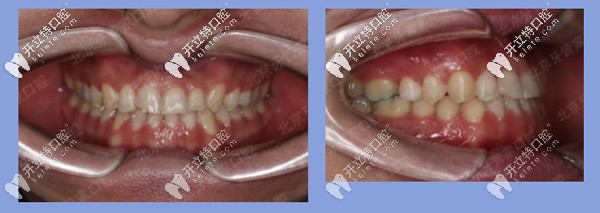

矯正結(jié)果:上下前牙反合解除,上唇突度恢復(fù)豐滿,患者非常滿意。

患者地包天矯正后

上面的是關(guān)于患者地包天的矯正案例。